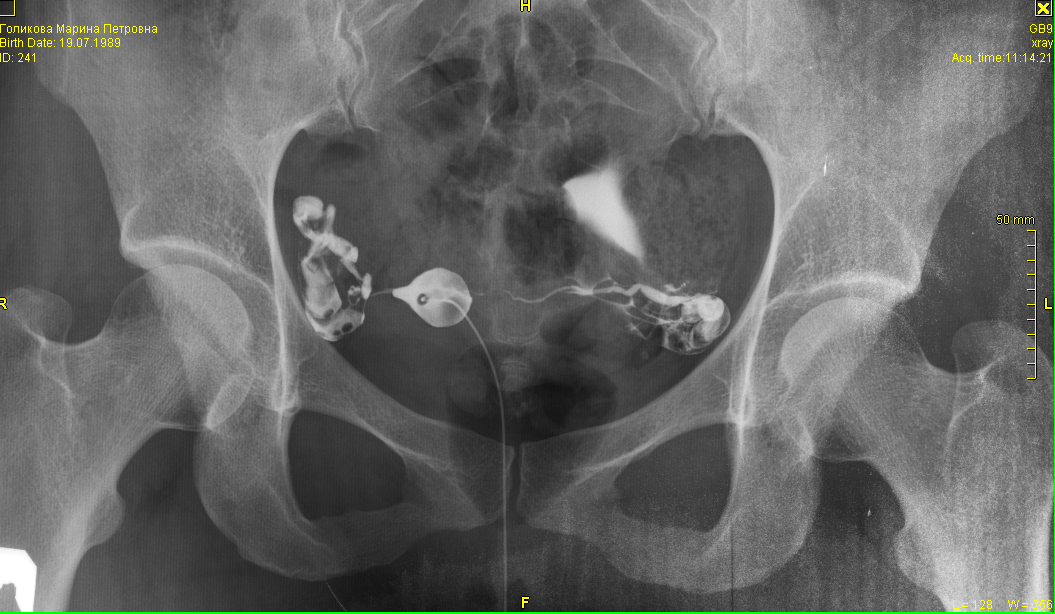

Гистеросальпингография: описание и фотографии